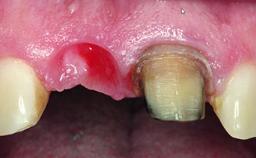

Replacement of an Ankylosed Upper Left Central Incisor: Bone Augmentation and Socket Grafting, Late Placement of an RC Bone Level Implant

A 15-year-old male patient was referred to us by his pediatric dentist in June 2004 for evaluation of treatment options for his failing tooth 21. The patient had recently seen an endodontist for internal bleaching and been advised that there had been significant resorption and ankylosis. The patient’s mother was concerned because the tooth appeared shorter than the adjacent one. His past dental history was significant for trauma (September 2001), where the tooth had been avulsed and reimplanted. Teeth 11 and 21 had been endodontically treated.

Bone Volume Deficient horizontally, requiring prior grafting

Esthetic Risk High